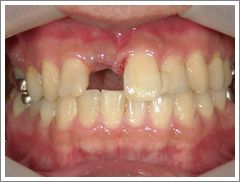

症例 5 外傷によって失った上の前歯に対してインプラント治療を行ったケース

治療前

外傷によって上の前歯が割れてしまい抜かなければならなかったケースです。インプラント治療によって隣の歯を削ることなく、審美的に前歯を回復させることができました。 ( 30代 男性 )